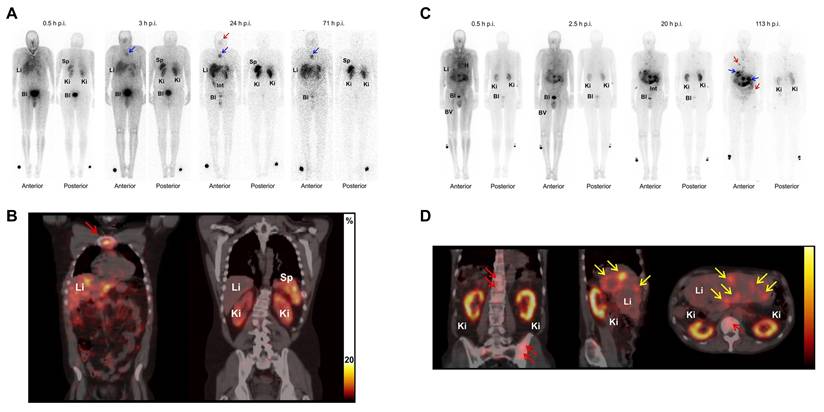

Patients with metastatic breast cancer (EGFR-positive)[111In]In-DTPA-hEGF demonstrated a favorable safety profile in a Phase I trial, with no administered activity-limiting toxicities up to 2290 MBq, rapid blood clearance, low administered activity to normal organs, and visible tumor accumulation in 47% of patients, although no objective tumor responses were observed.[22]

[111In]In-DTPA-NLS-TrastuzumabHER2Human breast cancer cell lines with HER2 positive (SK-BR-3, MDA-MB-361)Conjugation of [111In]In-DTPA-Trastuzumab with 6 NLS peptides enhanced nuclear localization in HER2-positive breast cancer cells (e.g., internalization in SK-BR-3 increased from 7.2% to 14.4%, and nuclear uptake in xenografts from 1.1% to 2.4-2.9%), resulting in up to a 6-fold increase in cytotoxicity compared with unlabeled trastuzumab and a 5-fold increase compared with [111In]In-DTPA-Trastuzumab.[115]

[111In]In-NLS-HuM195CD33Human leukemia cell line (HL-60)[111In]In-NLS-HuM195 achieved potent AML cell killing by increasing nuclear uptake up to 66% and reducing IC50 and IC90 values by over 50% compared to non-NLS controls, eliminating HL-60 colonies at 3.33 MBq/cell and showing no adverse effects in vivo, highlighting its therapeutic potential.[175]

Mitoxantrone-resistant HL-60 cell line (HL-60-MX-1)[111In]In-NLS-Trastuzumab significantly enhanced nuclear uptake and cytotoxicity against HL-60-MX-1 cells, with patient-derived AML specimens also showing variable but positive responses, suggesting efficacy against MDR phenotypes, including Pgp-170, BCRP1, and MRP1.[176]

[161Tb]Tb-[161Tb]Tb-DOTATOCSSTR-2/5Patient with paraganglioma (metastatic, well-differentiated, nonfunctional malignant) and neuroendocrine neoplasm of pancreas tail (metastatic, functional)A first-in-human study demonstrated that [161Tb]Tb-DOTATOC, synthesized with high radiochemical purity, enabled high-quality SPECT/CT imaging and detection of small bone and liver metastases at low administered activities, showing favorable biodistribution in the liver, kidneys, spleen, and bladder without any reported adverse effects.[177]

[161Tb]Tb-DOTATATESSTR-2Patients with NET (SSTR positive)Substitution of [177Lu]Lu- with [161Tb]Tb-DOTATATE Therapy boosts tumor absorbed dose per administered activity by approximately 40% (e.g., 2.9 → 4.1 Gy/GBq for a 10 g tumor), but to avoid increased kidney and bone marrow toxicity, the standard 7.4 GBq administered activity should be reduced to 5.3-5.4 GBq of [161Tb]Tb-DOTATATE.[178]

[161Tb]Tb-DOTA-cm09FRHuman nasopharyngeal/ovarian cancer cell line (KB/IGROV-1) with FR-positive[161Tb]Tb-DOTA-cm09 showed superior therapeutic efficacy than [177Lu]Lu-DOTA-cm09 both in vitro and in vivo, requiring significantly lower IC50 values in FR-positive tumor cells and delivering a higher tumor dose per administered activity (3.3 Gy/MBq vs. 2.4 Gy/MBq), while maintaining imaging capabilities and renal safety over a 6-month observation period.[179]

[161Tb]Tb-SibuDABPSMA (High affinity with albumin)Human prostate cancer with PSMA-positive (PC3-PIP)Compared to [177Lu]Lu- counterparts, [161Tb]Tb-SibuDAB and PSMA-I&T exhibited similar biodistribution but provided ~ 40% higher tumor-administered activities, with [161Tb]Tb-SibuDAB showing markedly enhanced tumor uptake (up to 69% IA/g) and therapeutic efficacy without observable toxicity in mice.[180]

Patients with mCRPC[161Tb]Tb-SibuDAB achieved superior tumor retention and absorbed dose per administered activity delivery (6.5 Gy/GBq, Th = 135 h) compared with [177Lu]Lu-PSMA-I&T (2.6 Gy/GBq, Th = 67 h) in the first mCRPC patient, with no acute toxicity despite modestly higher kidney (2.6 vs. 1.2 Gy/GBq) and parotid (0.5 vs. 0.3 Gy/GBq) absorbed doses administered activities (PROGNOSTIC Phase I clinical trial, NCT06343038).[181]

[161Tb]Tb-PSMA-617PSMA6 patients with mCRPC[161Tb]Tb-PSMA-617 showed superior efficacy in mCRPC patients, with a 2.4-fold increase in tumor absorbed dose per administered activity (6.10 ± 6.59 vs. 2.59 ± 3.30 Gy/GBq) and higher therapeutic indices for the kidneys (11.54 ± 9.74 vs. 5.28 ± 5.13 Gy/GBq) and parotid glands (16.77 ± 13.10 vs. 12.51 ± 18.09 Gy/GBq) (NCT04833517).[182]

[161Tb]Tb-DOTA-LM3SSTR-2Rat pancreas tumor cell line with SSTR-positive (AR42J)Dual-isotope SPECT/CT imaging in AR42J tumor-bearing mice demonstrated that [161Tb]Tb- and [177Lu]Lu-labeled somatostatin analogues (DOTATOC and DOTA-LM3) exhibited indistinguishable PK and sub-organ biodistribution, with DOTA-LM3 showing significantly higher tumor uptake than DOTATOC (e.g., > 20% IA/g vs. ~10% IA/g at 4 h post-injection).[183]

Patient with ileal NET (metastatic, hormone-active [carcinoid syndrome])Following administration of 1 GBq [161Tb]Tb-DOTA-LM3, the patient's liver metastases demonstrated a tumor half-life of 130 h and an absorbed dose per administered activity of up to 39 Gy/GBq, while bone marrow, kidney, and spleen absorbed doses per administered activity were 0.31, 3.33, and 6.86 Gy/GBq, respectively, accompanied by a chromogranin A decrease of 163 µg/L and minimal hematologic toxicity (NCT05359146).[184]